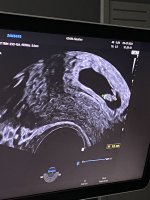

Syns det ble for lenge å vente til 25/8, så når jeg fant et annet sted med ledig time allerede på torsdag kapret jeg den i tillegg